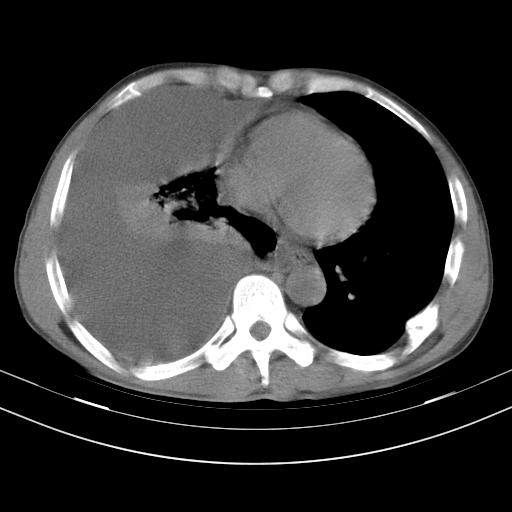

男性,44岁,结核病史多年。现胸闷气短,咳嗽,偶咳血。

右侧胸腔积液

右肺下叶不张

双肺多发结节影最分空洞形成考虑占位不除外结核

双肺陈旧性病变

1、右侧大量胸腔积液伴右肺压缩性膨胀不全,建议抽液治疗后复查 2、两肺继发性tb伴空洞形成。

1)两肺继发性肺结核伴空洞形成,左肺多发性结核球。2)右侧大量胸腔积液伴右肺部分膨胀不全。3)纵隔淋巴结肿大。

吉大一院胸水抽检结果:结核性胸水